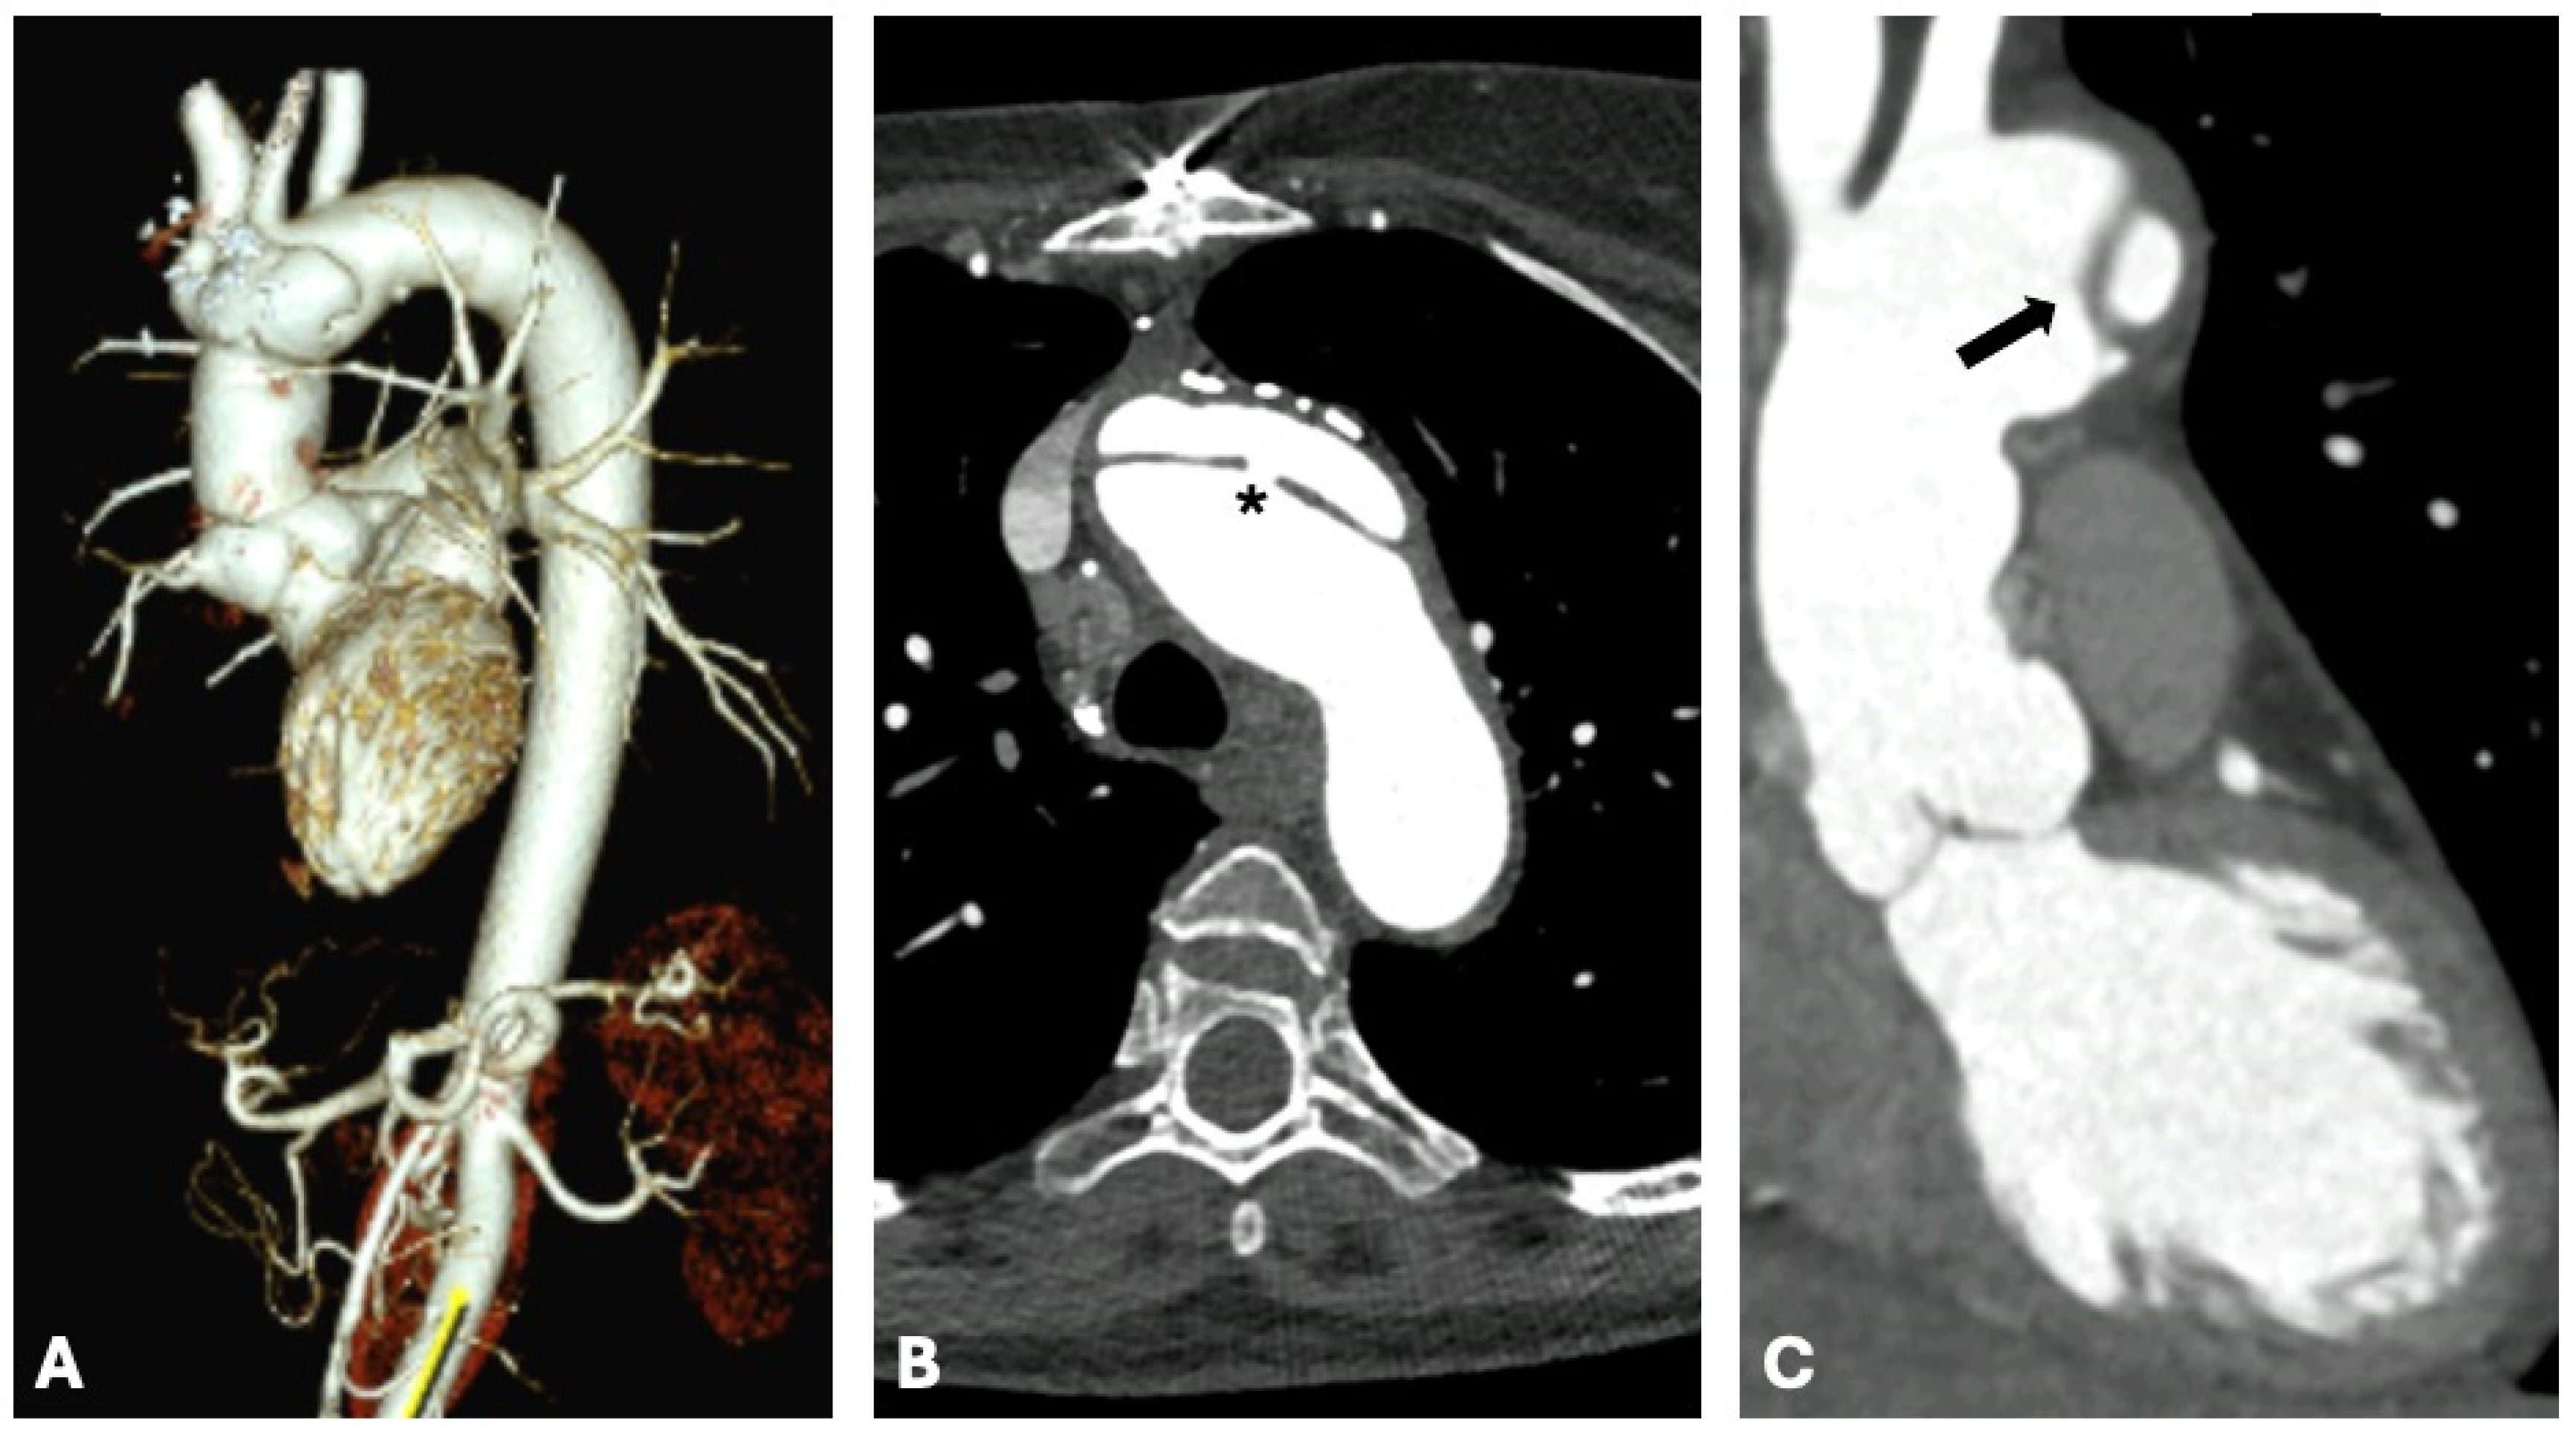

4. Computed Tomography Uses in Individuals with Marfan Syndrome

| Computed Tomography (CT) | Use CT for detailed evaluation of the entire aorta, particularly in emergencies like dissections. Perform assessments in multiple phases (non-contrast, arterial, and late) for accurate characterization of calcifications, intramural hematomas, and contrast leaks. Apply dose-reduction techniques to minimize radiation exposure, particularly in pediatric populations. Administer contrast tailored to patient size and condition (e.g., 2 mL/kg in children, 1.5 mL/kg in adults) with appropriate infusion rates for optimal imaging quality. Standardize aortic measurements in diastole, reporting dimensions consistently (e.g., outer-to-outer for thickened walls, inner-to-inner for routine measurements). Employ 3D reconstruction tools for surgical planning and follow-up monitoring. Integrate CT into longitudinal follow-up of aortic enlargement, particularly in cases where echocardiography alone provides inconsistent results. |